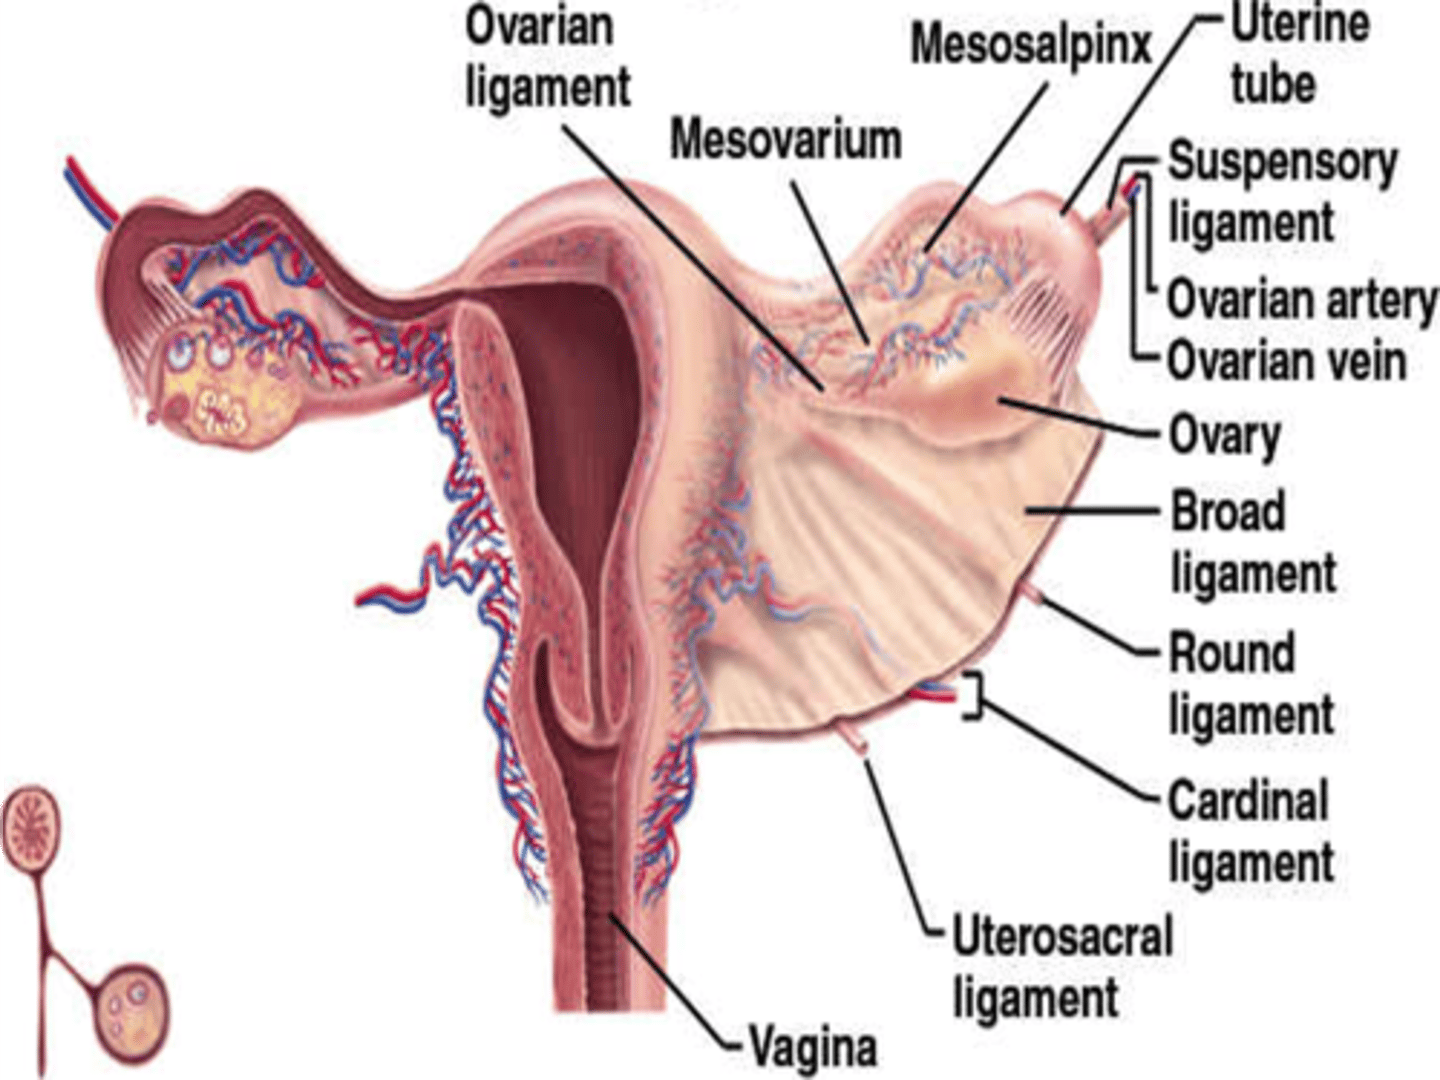

The broad ligaments extend between the ___ and ___

uterine body; ovary

What is positioned between the 2 layers of the broad ligaments?

fallopian tubes

round ligament

ovarian ligament vascular structures

The round ligaments are located ___ to the fallopian tubes and insert into the ___ to help maintain the ___ of the uterus

anteroinferior; labia majora; position

The ovarian ligaments are located ___ at the ___ of the uterus

bilaterally; cornua

The suspensory ligaments extend from the ___ to the ___

infundibulum; pelvic sidewall